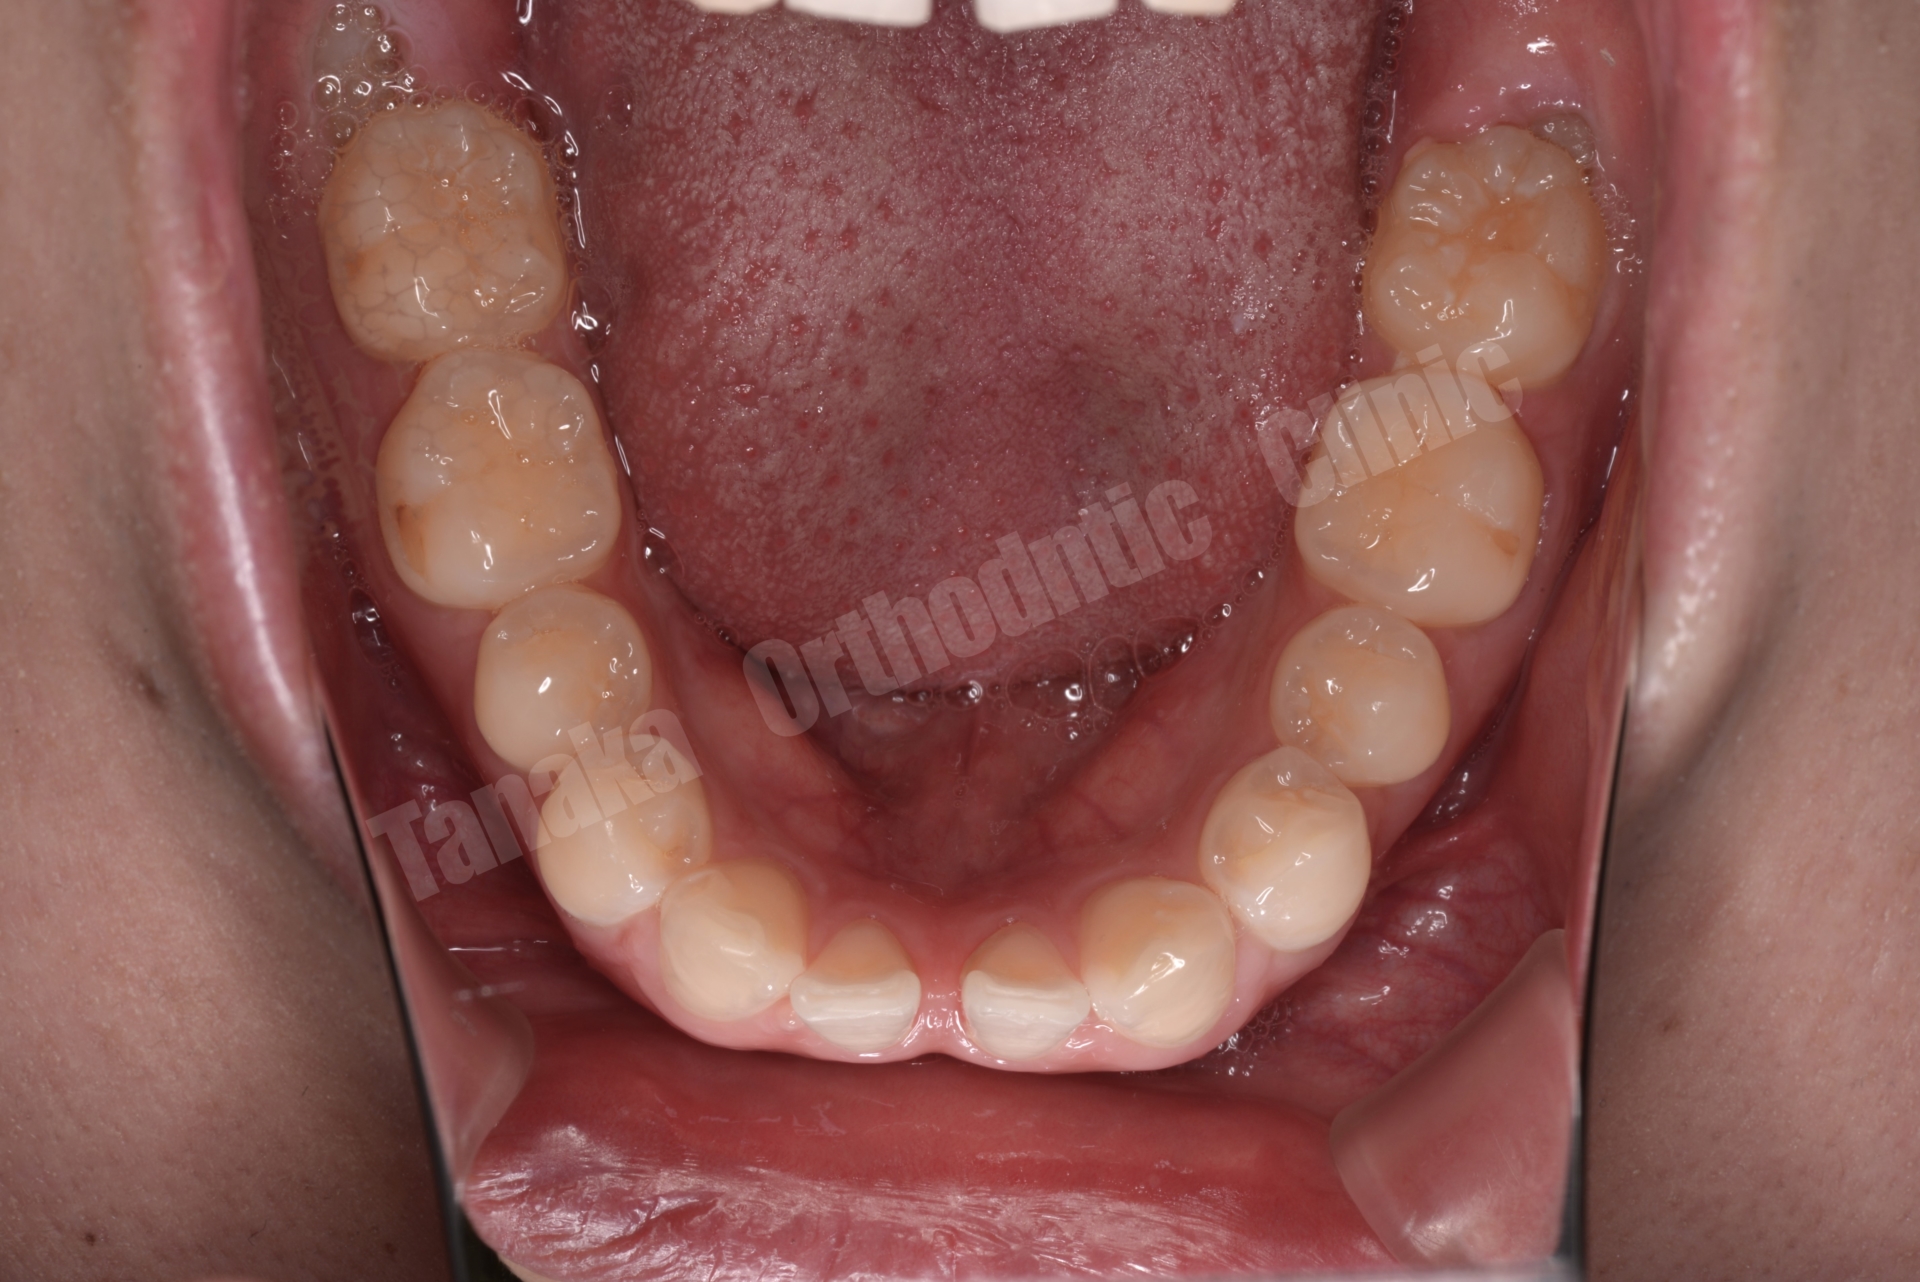

【治療前】

| 診断 | 下顎前歯の先天欠如(2本)によるスペースドアーチ、上顎前歯の唇側傾斜、前歯部水平被蓋が大きい、上顎前歯部叢生、両側AngleⅡ級、上下顎両側8番の埋伏歯、全体的に歯根が短い |